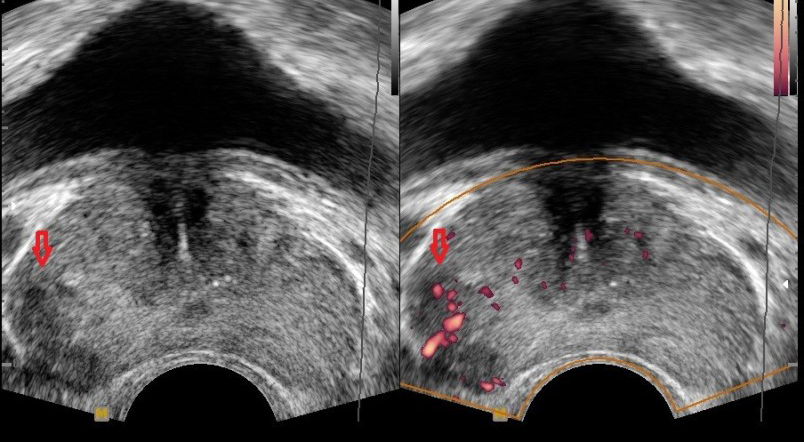

- 정기적인 검진: 특히 50세 이상 남성은 정기적인 전립선 검진을 통해 미리 질환을 예방해야 합니다.